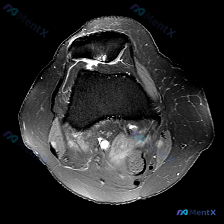

看到这个挺有代表性的读片病例,整理一下资料和分析思路分享给大家。 病例基础信息 这是一份单张膝关节MRI轴位T1加权序列影像,临床怀疑存在软骨异常,要求读片分析。 影像学读片结果 解剖结构评估 1. 骨性结构:髌骨形态完整,皮质连续,骨髓信号无异常;髌股关节对合关系大致正常,无半脱位;股骨远端滑车区...

今天遇到一个有意思的读片问题:只给了一张膝关节轴位MRI,问这里有没有软骨异常,整理一下分析思路分享给大家。 基本病例/影像信息 提供的是膝关节单张轴位MRI扫描图像,可识别的解剖结构包括:前方的髌骨、中部的股骨内外侧髁与髁间窝、髌股关节间隙,以及周围部分软组织。 客观影像所见 1. 软骨结构:髌骨...

看到一个很有讨论意义的膝关节影像病例,整理出来和大家分享一下。 病例基本信息 核心问题:临床怀疑存在膝关节软骨异常,仅提供单张膝关节MRI T1序列轴位影像进行分析。 影像学读片结果 这张影像为髌股关节层面的轴位T1加权像,读片结果如下: 1. 骨骼结构:髌骨、股骨内外侧髁形态完整,皮质骨连续,松质...

最近遇到一个有意思的读片病例:临床怀疑髌股关节软骨异常,但给出的单张T1加权轴位MRI却没看到明确病灶,整理一下整个分析思路分享给大家。 一、病例影像基础信息 这是一份膝关节MRI检查的T1加权轴位(横断面)图像,扫描层面位于髌股关节水平,先整理一下基础读片结果: 1. 解剖结构确认:前方为髌骨,后...